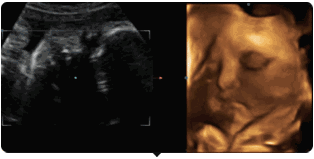

你可以通过美国GE-730高清四维彩超

看到胎宝宝最可爱撩人的画面——

麻麻,我在咬手指哟!